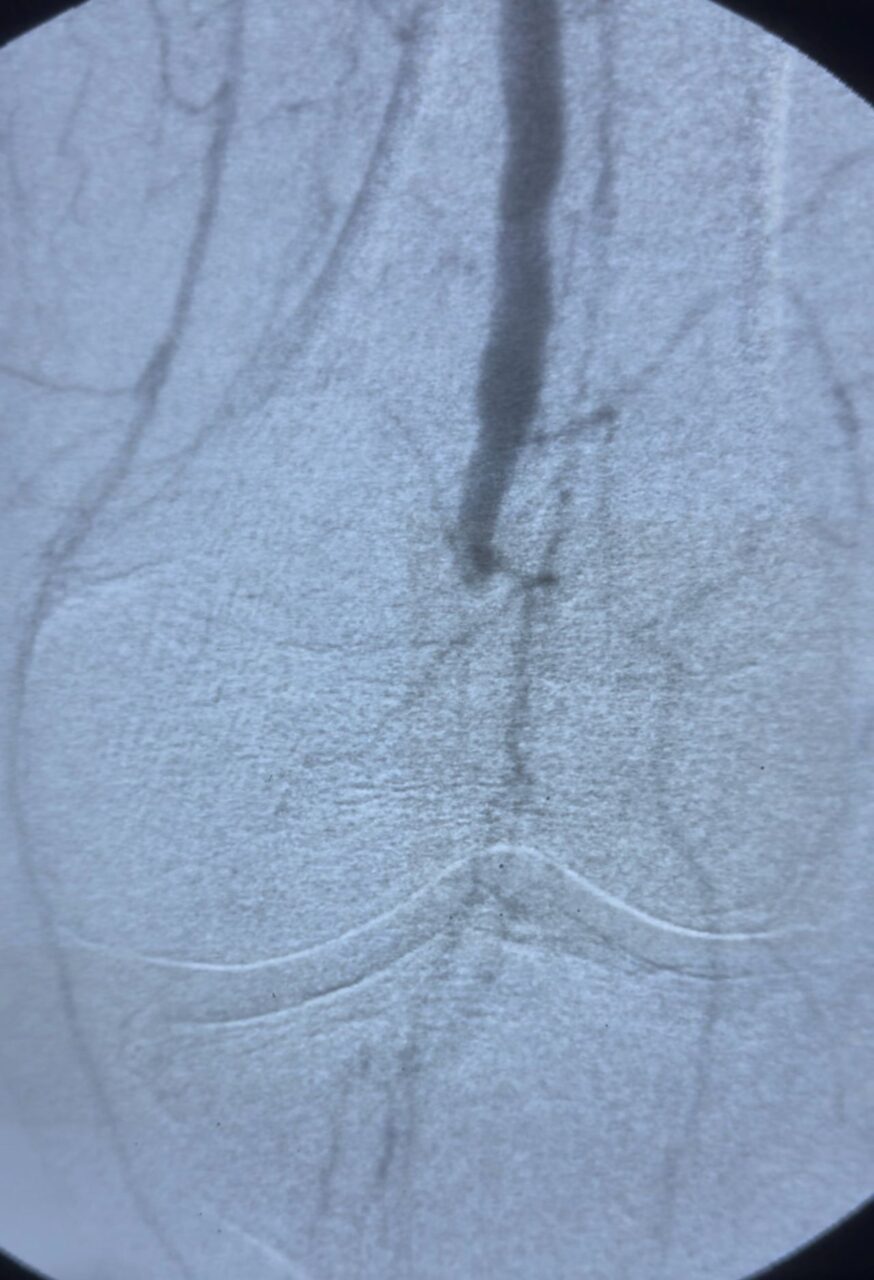

“Patient with subacute massive arterial thrombosis, documented from the distal superficial femoral artery down to the infragenicular level.

A combined antegrade and retrograde approach was performed. Through the pedal access, multiple atheromatous occlusions were identified in the anterior tibial artery. A balloon was inflated and left in place across the anterior tibial artery arch to protect the distal axis from embolization during thromboaspiration.

Using a manually modified 5F multipurpose catheter connected to a 50 cc syringe, negative-pressure aspiration was performed from the femoral to the popliteal artery, effectively removing extensive thrombotic material.

Final outcome: complete recanalization of the femoral, popliteal, and anterior tibial arteries, with restored distal flow.